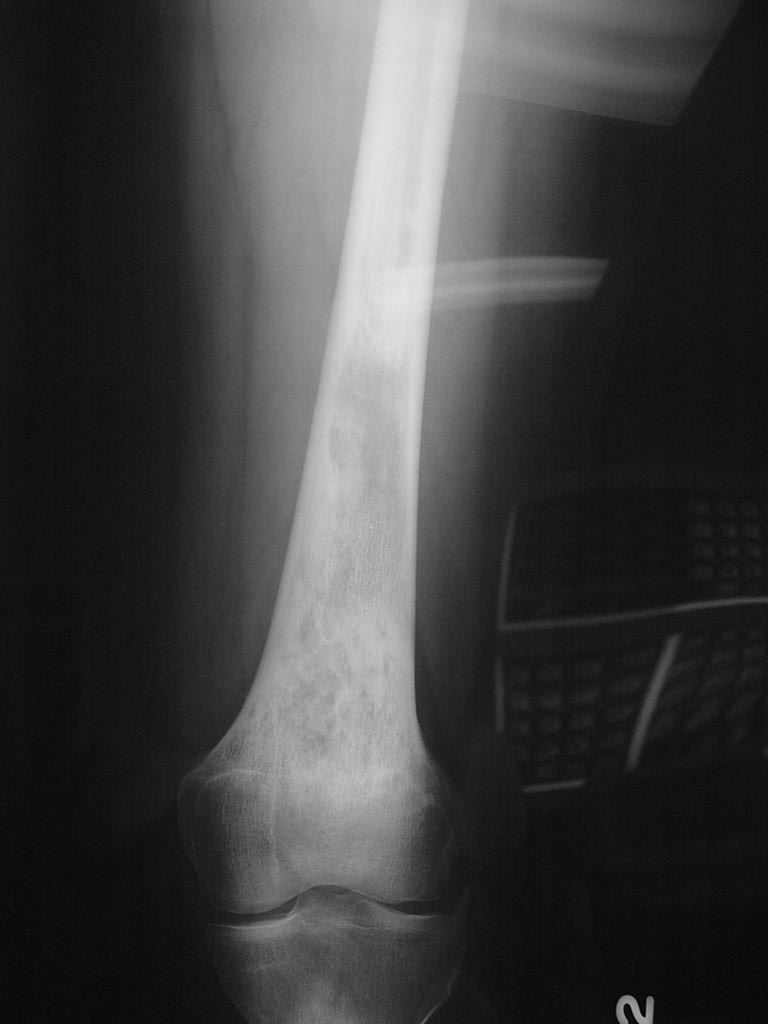

12A)Plain Radiograph Of Epithelioid Hemangioendothelioma Of Femu (1)

Radiographic imaging is used to help form a diagnosis. These include X-Ray, MRI, CT and Bone Scans

An example of an X-Ray is shown.